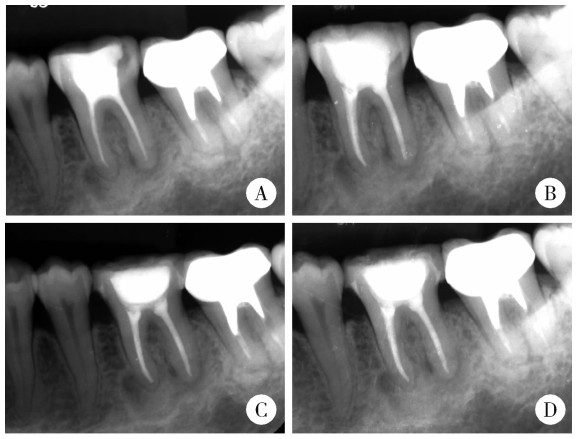

Figure 4

Panoramic radiograph at 1-year follow-up"